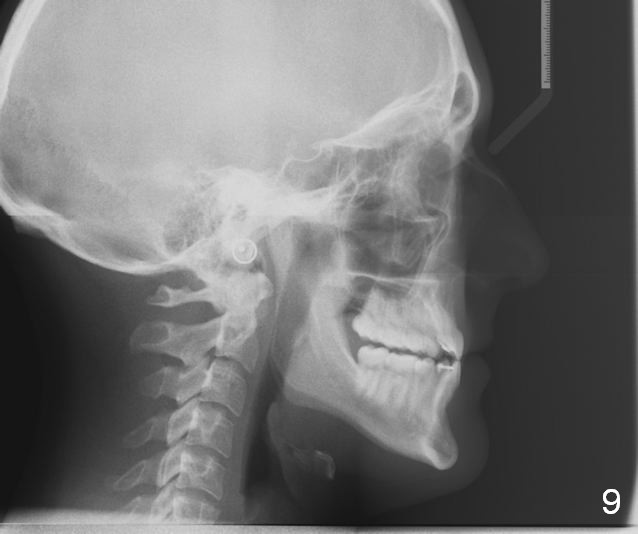

Maxillary Retrusion Post-Orthodontic Treatment

Initial information was obtained on 02/26/2014 (Fig.1-10). Anterior edge-to-edge and Posterior Open Bite (Fig.4 *): unfavorable differential Class III growth after orthodontics as a child.